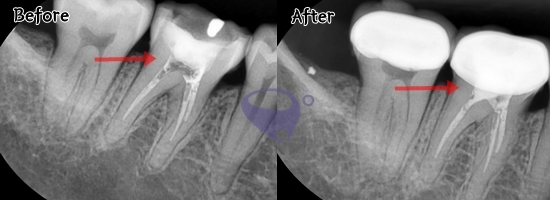

신경치료는 충치가 치수 조직까지

감염시켰을 때 진행하게 되는데요.